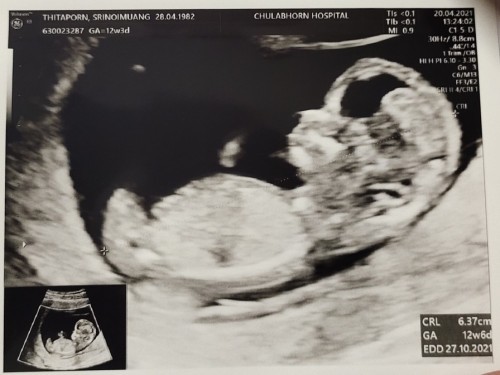

12Wค่ะ

3เดือนแล้วค่ะ..เริ่มเห็นแขน ขา บ้านใหนเหมือนกันมั๊ยค่ะ???3เดือนเห็นชัดขนาดนี้เหมือนกันรึป่าวค่ะ